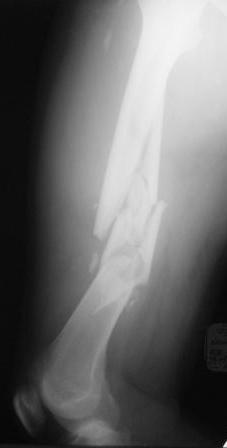

Re: Нужен совет по тактике лечения многооскольчатого перелома бедра

Выбор на пластине основан на том, что проксимальный отломок не цельный, по рентгенограмме видно, что в нём практически до малого вертела имеется осколок. Поэтому у меня опасения, что фиксация внутрикостного стержня в проксимальном отломке не будет достаточно стабильной.